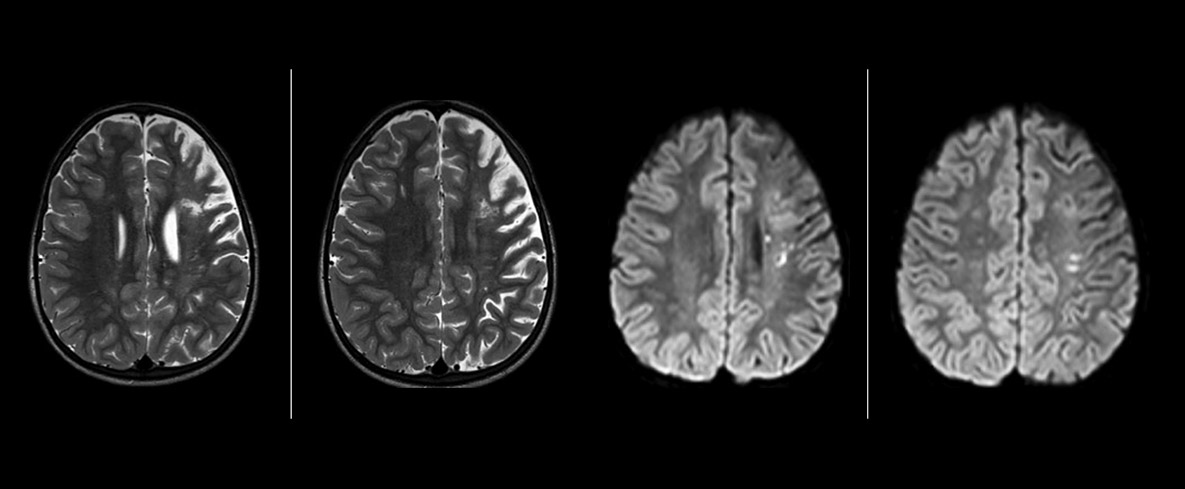

“La SWIp nous aide à identifier le sang ou les produits sanguins, la calcification et les maladies qui touchent le système vasculaire”, indique le Dr Miller. “Chez les enfants atteints de traumatisme crânien, elle met en évidence les zones affectées mieux que certaines des techniques que nous utilisions auparavant. Ces enfants présentent souvent des micro-lésions qui endommagent légèrement le sang et les tissus. L’utilisation de la SWIp nous aide à mieux caractériser l’étendue et la nature de la lésion. La caractérisation optimale d’une lésion favorise la fiabilité du diagnostic.”

“Je recommande vraiment aux autres utilisateurs d’adopter la SWIp. À l’origine, nous avions ajouté la séquence SWIp après nous être renseignés sur son utilité dans la littérature. Ensuite, nous avons directement comparé la SWIp aux séquences 2D à écho de gradient que nous utilisions. Après de nombreuses expériences cliniques pour en observer les avantages, nous étions assez confiants pour remplacer les anciennes séquences par des SWIp. Cela nous apporte une meilleure évaluation des processus physiologiques du cerveau qui étaient moins visibles sur nos anciennes séquences d’imagerie”, déclare le Dr Miller. “La SWIp est désormais notre séquence de base pour examiner les patients victimes de traumatismes crâniens au PCH, et nous l’utilisons épisodiquement pour les patients atteints d’anomalies vasculaires intracrâniennes.”

“Je crois que la SWIp est rapidement en train de devenir la norme dans l’imagerie des traumatismes crâniens grâce à sa haute sensibilité aux produits sanguins veineux. La SWIp peut même aider à attirer les patients ; nos neurochirurgiens nous demandent souvent d’examiner leurs patients sur nos scanners avec des techniques hautement sensibles comme la SWIp. On constate également une application grandissante des séquences SWIp sur d’autres anomalies vasculaires grâce aux possibilités d’évaluation physiologique du cerveau, par rapport à une imagerie structurelle standard.”